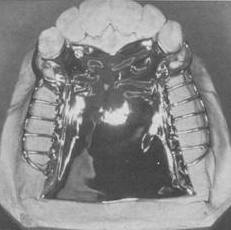

| Placa palatina

La placa palatina completa es especialmente indicada cuando se necesita

máximo apoyo en los tejidos palatinos.

En particular, deben ser los principal

conector de elección en casos de larga extensión distal, con 6 o menos dientes anteriores.

Se debe seleccionar en

los pilares que son periodontalmente afectados, lo que requiere

distribución de la máxima presión sobre el paladar.

Se utiliza, dónde están las zonas desdentadas

cubiertas con tejido flácido o cuando hay una bóveda

palatina

plana,

este conector también proporciona una mayor estabilidad.

La

placa palatina completa

no se utiliza en la presencia de torus palatino.

El conector palatino completo debe ser fabricado de una delgada placa de

metal de manera uniforme con precisión para reproducir la anatomía

del paladar.

Debe

cubrir la misma superficie que una prótesis completa superior.

La gran superficie de contacto con la

mucosa mejora el potencial de retención.

Conectores de este tipo son generalmente de metal fundido.

Sin embargo, una placa de acrílico se pueden utilizar

en las prótesis provisionales.